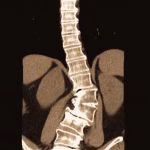

O Neurocirurgião especialista em coluna está apto a realizar o diagnóstico e tratamento de todos os problemas desse órgão, tanto o tratamento cirúrgico, quanto o clínico (tudo que não envolve cirurgias). Realiza o tratamento de doenças degenerativas (como hérnia de disco, estenose de canal lombar, espondilolistese), escoliose, tumores, fraturas, entre outros.

- Canal lombar estreito